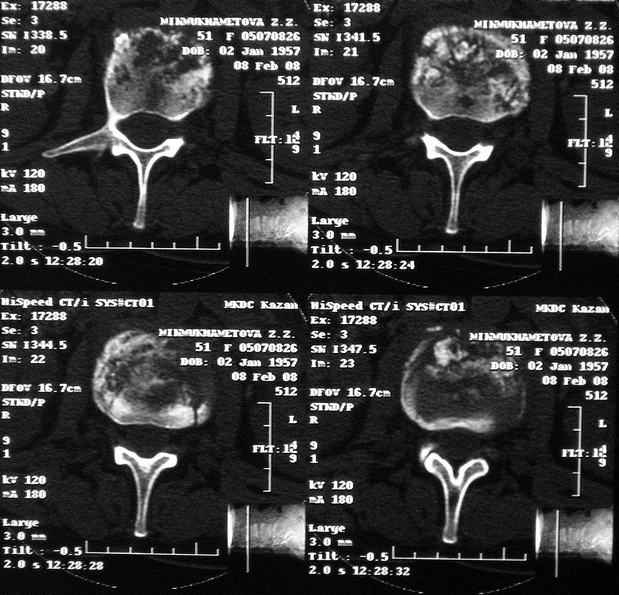

MRI через три недели

|

По данным представленных КТ и МРТ у больной имеется достаточно выраженная степень деструкции тел позвонков (около 30% общей костной массы тела позвонка), что определяет высокий риск возникновения патогических переломов и появления локальной кифотической деформации на этом уровне.

Уважаемый доктор! судя по последнему МРТ процесс затрагивает соседние позвонки с переходом процесса через диск. Для туберкулёза как раз и характерна картинка "целующихся" позвонков. При бактериальном процессе диск страдает лишь вторично. Туберкулиновые пробы могут быть в пределах нормы, лёгкие - чистые. Вообще туберкулёз последнее время стал очень коварен и атипичен. Такие случаи отмечались у детей старшего возраста.